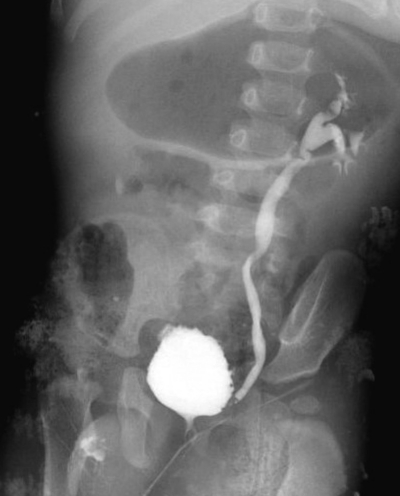

尿所見:蛋白 1+、糖 (-) 、潜血 1+、沈渣に赤血球 1〜4 /HPF、白血球 50〜99/HPF。血液所見:赤血球 488 万、Hb 12.4 g/dL、Ht 37 %、白血球 14,800、血小板 30 万。血液生化学所見:総蛋白 6.9 g/dL、AST 29 U/L、ALT 18 U/L、尿素窒素 mg/dL、クレアチニン 0.5 mg/dL。CRP 8.6 mg/dL。尿沈渣の Gram 染色で Gram 陰性桿菌を認めた。急性腎盂腎炎と診断し、抗菌薬で治療を行った。解熱後の排尿時膀胱尿道造影像を別に示す。

適切な治療法はどれか。

e. 膀胱尿管逆流防止術